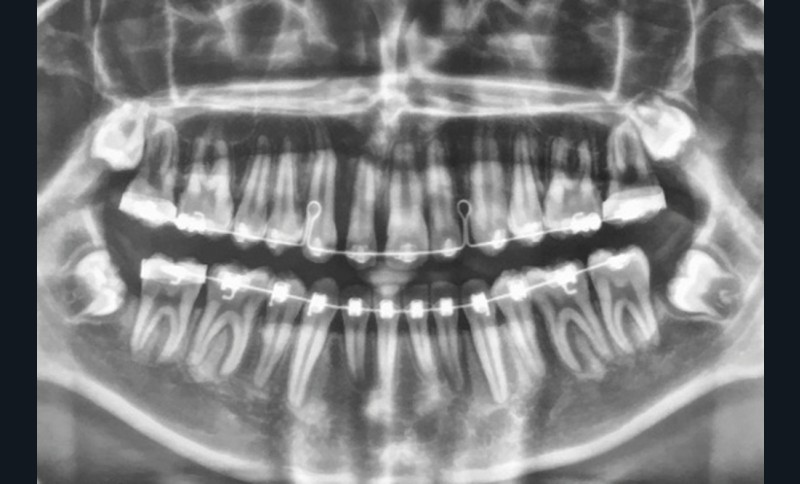

Son incisive centrale supérieure droite (11) présente un défaut de structure amélaire sévère, compromettant une technique restaurative pérenne a minima. L’examen de la panoramique (fig. 1e) et de la radiographie rétroalvéolaire de 11 (fig. 1f) objective une fracture coronaire verticale, ainsi qu’une racine grêle et courbe, peut-être en rapport avec un ancien traumatisme [1]. Le rapport couronne clinique/racine clinique est défavorable.

Lors de la phase de finitions, une séance de réévaluation radiographique des axes radiculaires (fig. 3a-b) a permis de corriger les défauts de collage et d’étudier les mouvements squelettiques et dento-squelettiques obtenus.